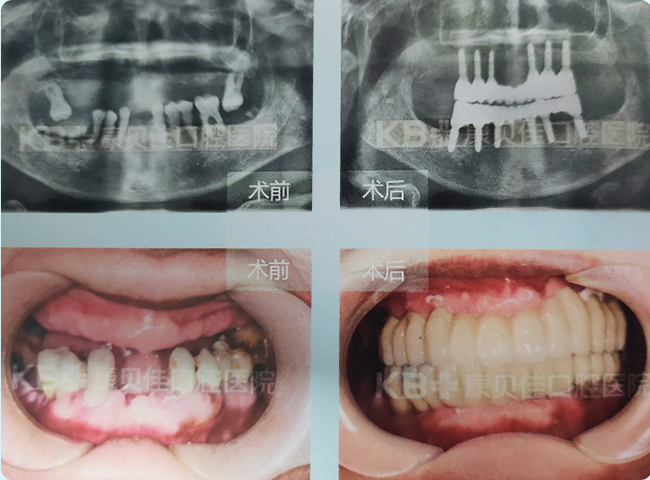

刘女士 57岁

因为缺一两颗牙时没有引起重视导致牙齿越缺越多,仅剩的几颗牙也摇摇欲坠,平时只能吃一些软烂的食物,非常痛苦。由于缺牙时间比较长牙槽骨条件不好,种植难度非常大,到康贝佳采用种植12颗即刻恢复技术恢复了满口牙。

治疗方案:

上颌种植6颗恢复半口牙 下颌种植6颗恢复半口牙